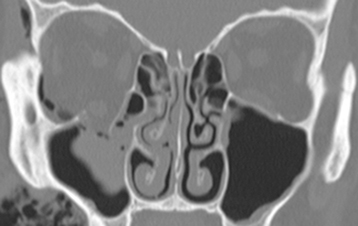

Figure 14.2.3: Coronal bone window of the patient seen in Figure 14.2.2 shows the fracture again.

In bone windows, the soft tissue detail fades, but bone detail is enhanced, allowing for better examination of bony anatomy.